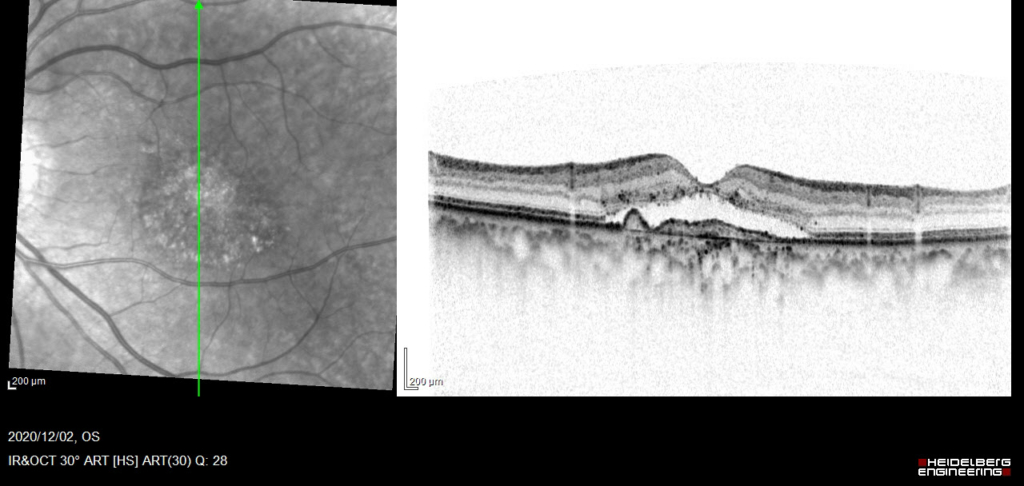

網膜色素上皮 RPE異常の部位で、低~軽度高蛍光を示す。

漿液性網膜剥離 Serous Retinal Detachment(SRD)がみられる。RPEは不正に隆起し、double-layer sign(RPEを示す高反射層とそれより外層にみられる高反射層の間に間隙がみられる)がみられ、CNVの存在を示す。